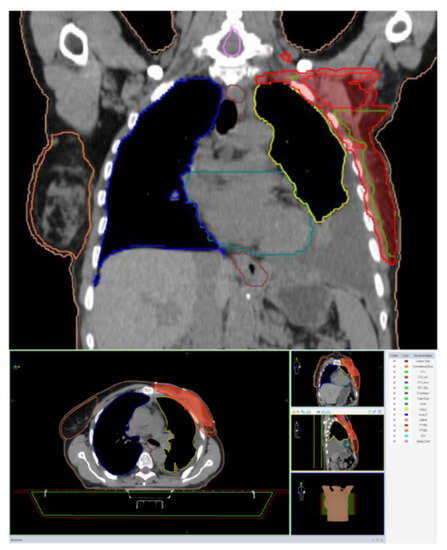

2. Case Report